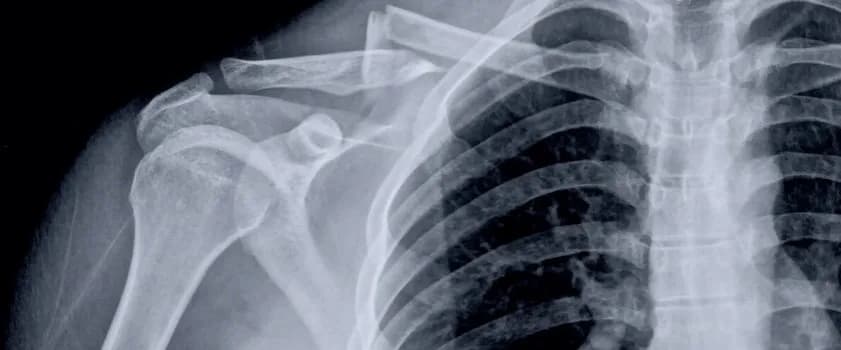

Złamany obojczyk - Wskazania do operacji i przebieg leczenia

Operacja złamanego obojczyka często konieczna przy przemieszczeniu odłamów kości. Poznaj wskazania do zabiegu oraz techniki chirurgiczne, jak operacja przepukliny przełyku czy złamanie kostki bocznej operacja.